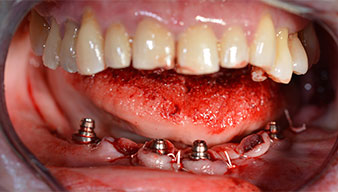

Un CT Scan à faisceaux coniques tridimensionnel (CBCT, Planmeca) a été réalisé au préalable afin de réduire les risques. Il a révélé une qualité et une quantité d'os disponible suffisante pour l'intervention chirurgicale et la restauration immédiate par la méthode All-on-four. En suivant le protocole de ce concept, les implants sont insérés au niveau de 35, 32, 42 et 45 en inclinant les implants distaux jusqu'à 45°, le profil d'émergence se déplace ainsi vers l'arrière et produit un polygone de stabilisation plus large (Fig. 3).

Fig. 3

Les piliers angulés (35°) ont été vissés pour compenser la divergence des implants distaux. Ainsi, le profil

d'émergence de tous les implants doit être le plus perpendiculaire possible par rapport au plan occlusal. Il s'agit

d'une condition préalable à la pose en occlusion de la prothèse provisoire puis permanente (Fig. 15 et 16).

Implants

Fig. 15

Fig. 16